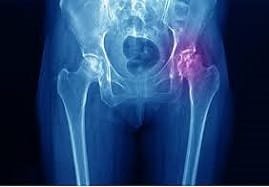

A joint X-ray may be necessary to identify arthritis-related joint damage to access the gravity of the pain.

If your doctor suspects there’s another cause, they may order a blood test to screen for certain autoimmune disorders. They may also request a sedimentation rate test to measure the level of inflammation in the body or a complete blood count.